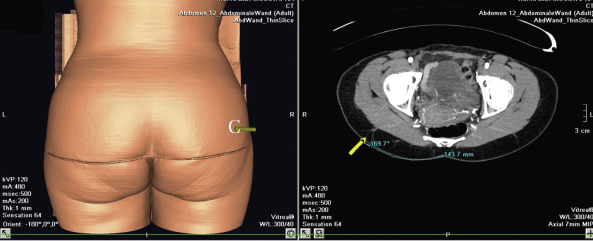

In the case of a perforator flap, a fusiform skin island is drawn over the perforators, ideally centered on selected perforators. The main perforators are localized by a handheld 5–8 MHz Doppler probe in an area above or under the piriform muscle, for SGAP or IGAP flaps, respectively ( Fig. 44.3C ). Currently, we are using a new method for perforator mapping with a 64-slice spiral computed tomography (CT) scan ( Figs 44.4 , 44.5 ). This provides more accurate information concerning the vascular network and perforators. Choice of the perforator depends not only on the strength of the Doppler signal or the findings of the CT scan but also on the location of the perforator. Choosing the most remotely located perforator from the SGA exit will provide a longer pedicle, which is more suitable for microanastomosis ( Figs 44.4 , 44.5 ).

In the case of perforator flaps, the preoperative markings are adjusted, depending on the location of the perforators. The patient is positioned lying on the operative table ( Fig. 44.3C ). A line is drawn between the PSIS and the coccyx (PSIS-C). The position of the piriform muscle is located by connecting the middle of the PSIS-C line with the superior edge of the greater trochanter (T) of the femur. The relatively constant anatomy of the superior gluteal artery and the presence of a low number of perforators that cross the fascia perpendicularly make it rather easy to preoperatively identify the location of the perforators by unidirectional Doppler flowmetry or spiral CT scanner.